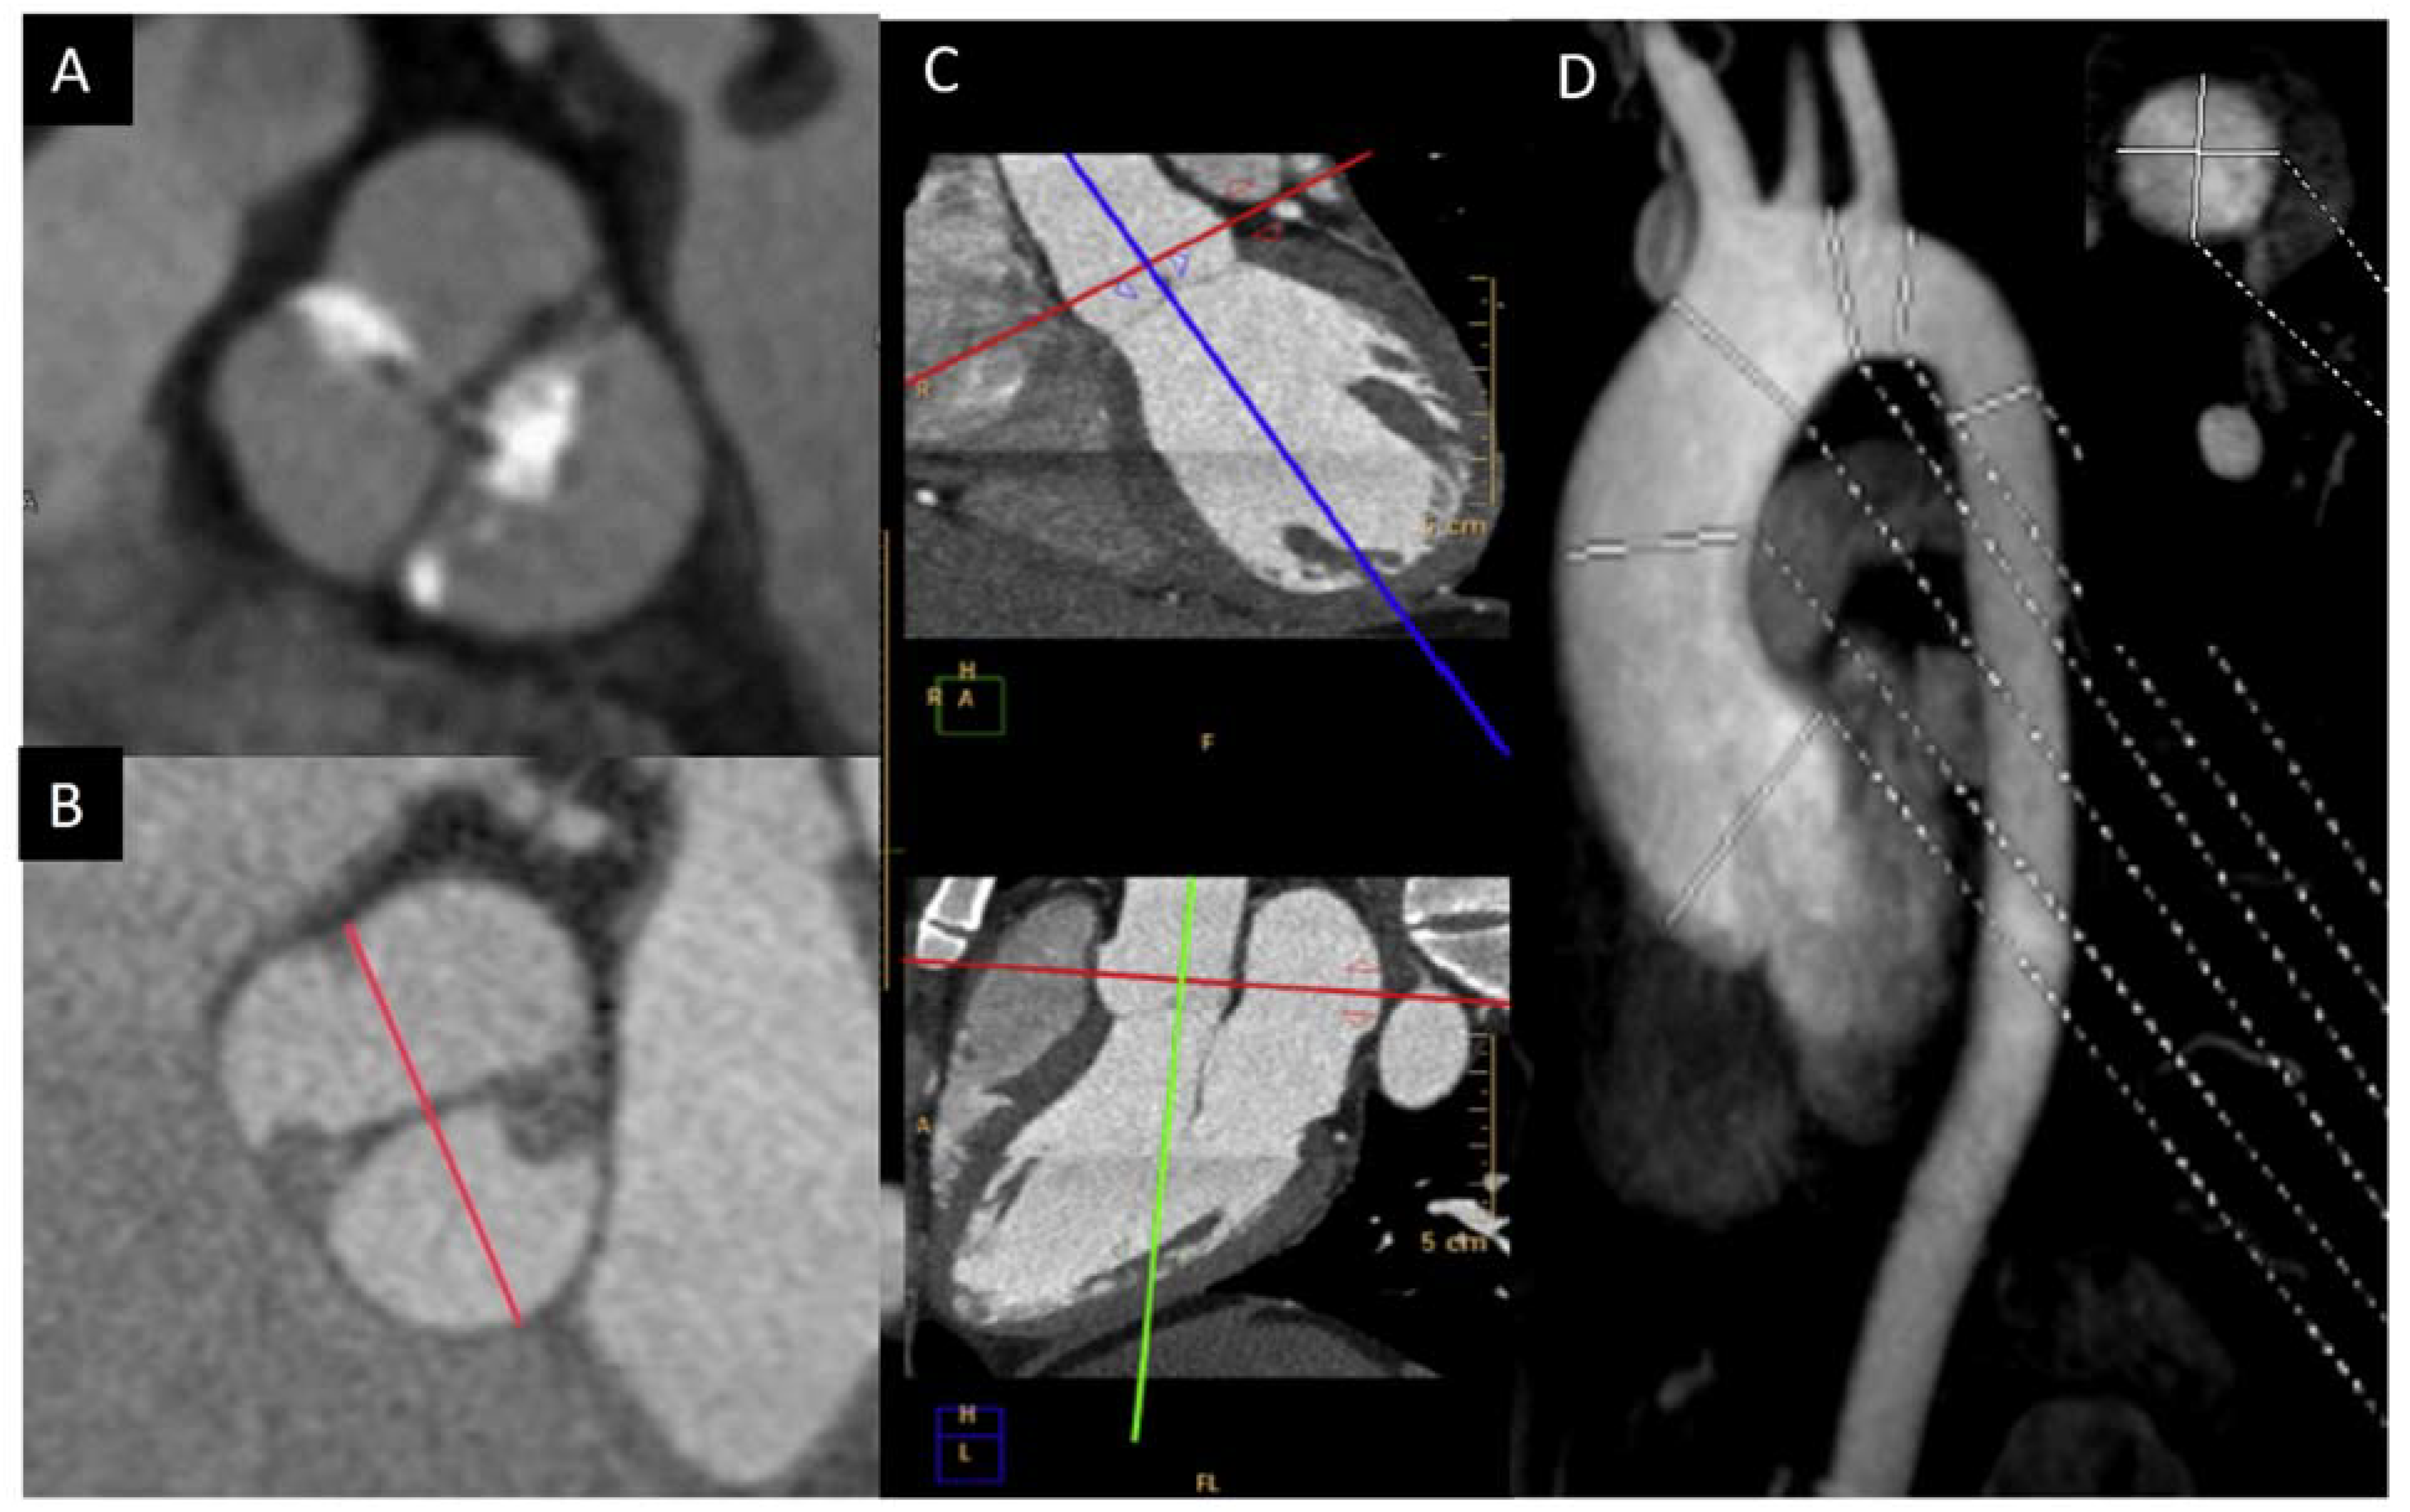

2. Diagnosis and BAV Phenotype

4.1. Valve Calcification

4.2. Aortic Stenosis

- A major benefit of CT is its superior spatial resolution, by which the aortic valve can be evaluated for morphology and calcification, ascending aorta size accuracy, and reproducibility measured and coronary arteries assessed.

- Rodriguez-Palomares, J.F.; Teixido-Tura, G.; Galuppo, V.; Cuellar, H.; Laynez, A.; Gutierrez, L.; Gonzalez-Alujas, M.T.; Garcia-Dorado, D.; Evangelista, A. Multimodality Assessment of Ascending Aortic Diameters: Comparison of Different Measurement Methods. J. Am. Soc. Echocardiogr. 2016, 29, 819–826.e4. [Google Scholar] [CrossRef] [PubMed]